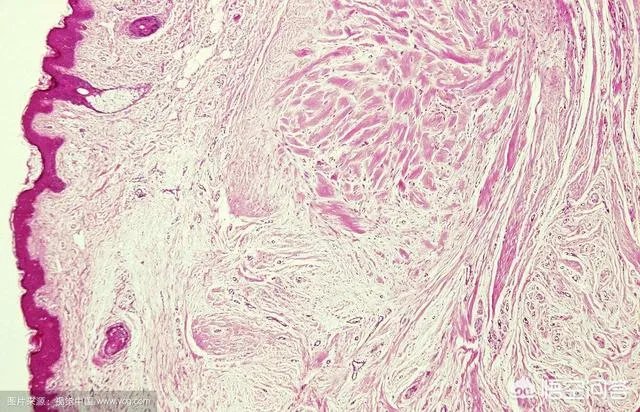

皮肤瘢痕疙瘩是当瘢痕组织生长超过创口部位向周围正常组织浸润或瘢痕生长时间超过正常生长期时就成为瘢痕疙瘩,又称为蟹足肿或瘢痕瘤,属于皮肤纤维增生性疾病或真皮纤维化疾病。

瘢痕疙瘩常见于青壮年,两性均可累及。前胸、后背和上臂双腮部,耳部等处为好发部位,有时也见于臀部。皮损表现为境界清楚、高出于皮面的瘢痕性斑块、结节甚至肿块,形状可不规则,有时边缘呈蟹足状向外延伸扩展。

皮损在增生期常呈红色,表面可有毛细血管扩张,以后颜色转暗,有时较大皮损边缘区处于增生期而呈红色,但皮损中央因处于静止期而颜色接近于正常肤色。